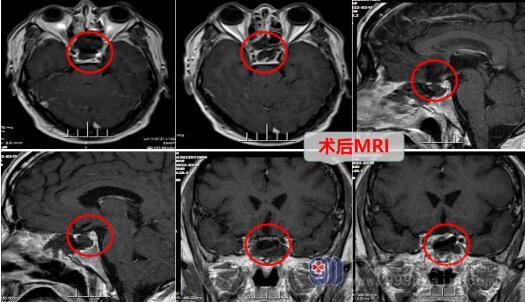

听完医生解释,钟先生在完善了相关检查与术前准备后,接受了神经外十科团队为他行“内镜经鼻蝶鞍区占位病变”,手术很顺利,肿瘤被完整的切除了。术后的钟先生精神良好,没有明显的不适,顺利进入了康复阶段。

神经外十科团队对经鼻蝶鞍区占位切除的经验十分丰富,此手术方法是鞍区占位(垂体瘤、颅咽管瘤、鞍结节脑膜瘤等)的特色治疗手段,与传统的开颅手术对比,有更高治疗质量的同时,能减少患者的痛苦。